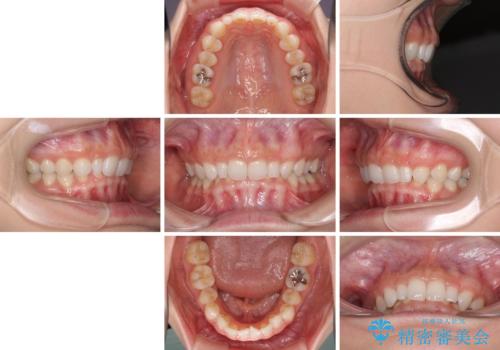

前歯のデコボコと小さい歯を改善 インビザラインとオールセラミッククラウン

- 前歯のデコボコと左右の矮小歯を気にして来院された患者様です。

矮小歯の前後にスペースを作るようにインビザライン矯正治療を計画し、矯正治療後にオールセラミッククラウンによる補綴治療を行うこととしました。

アンカースクリューを用いて上顎歯列全体を後方移動させ、極力過蓋咬合も改善されるよう計画しました。

インビザラインは長時間装着を自己管理する必要がありますが、残念ながら十分な時間の装着を行うことができませんでした。

何とか矮小歯を改善するスペースを作ることはできましたが、過蓋咬合を改善するには至りませんでした。